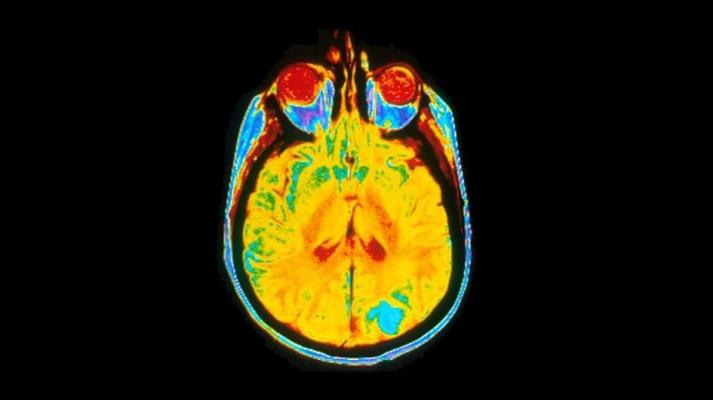

A single image of a human brain using a magnetic resonance imaging (MRI) machine. Image courtesy of Dr Leon Kaufman. University Of California, San Francisco